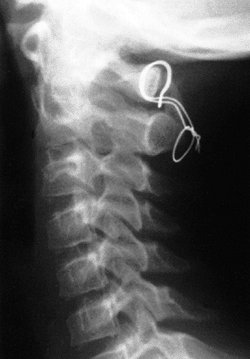

Figure 22.4 Lateral flexion (A and extension) B

radiographs of an 11-year-old boy with Down syndrome. The child presented with loss of hand control when flexing his neck. Using the method of Tredwell et al. (37), the atlantooccipital distance is measured as the distance between the anterior margin of the condyles at the base of the skull and the sharp contour of the anterior aspect of the concave joint of the atlas. More than 4 mm of posterior translation is abnormal. The atlantooccipital distance (arrows) measures 10 mm in extension and 1 mm in flexion. The atlantodens interval is 1 mm in extension and 6 mm in flexion, for a total of 5 mm of motion (arrowheads). The space available for the cord is 17 mm in flexion and 20 mm in extension. Both occipitoatlantal instability (more than 4 mm posterior translation) and atlantodens hypermobility (5 mm atlantodens interval in flexion) are present. |